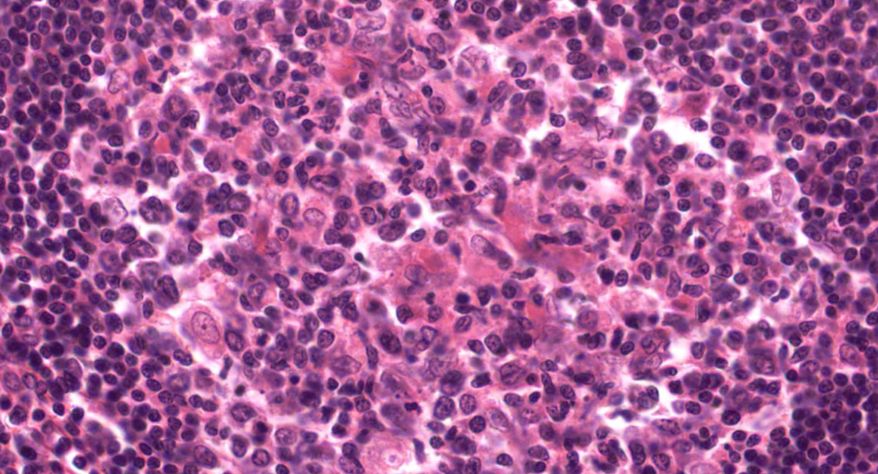

4 霍奇金淋巴瘤